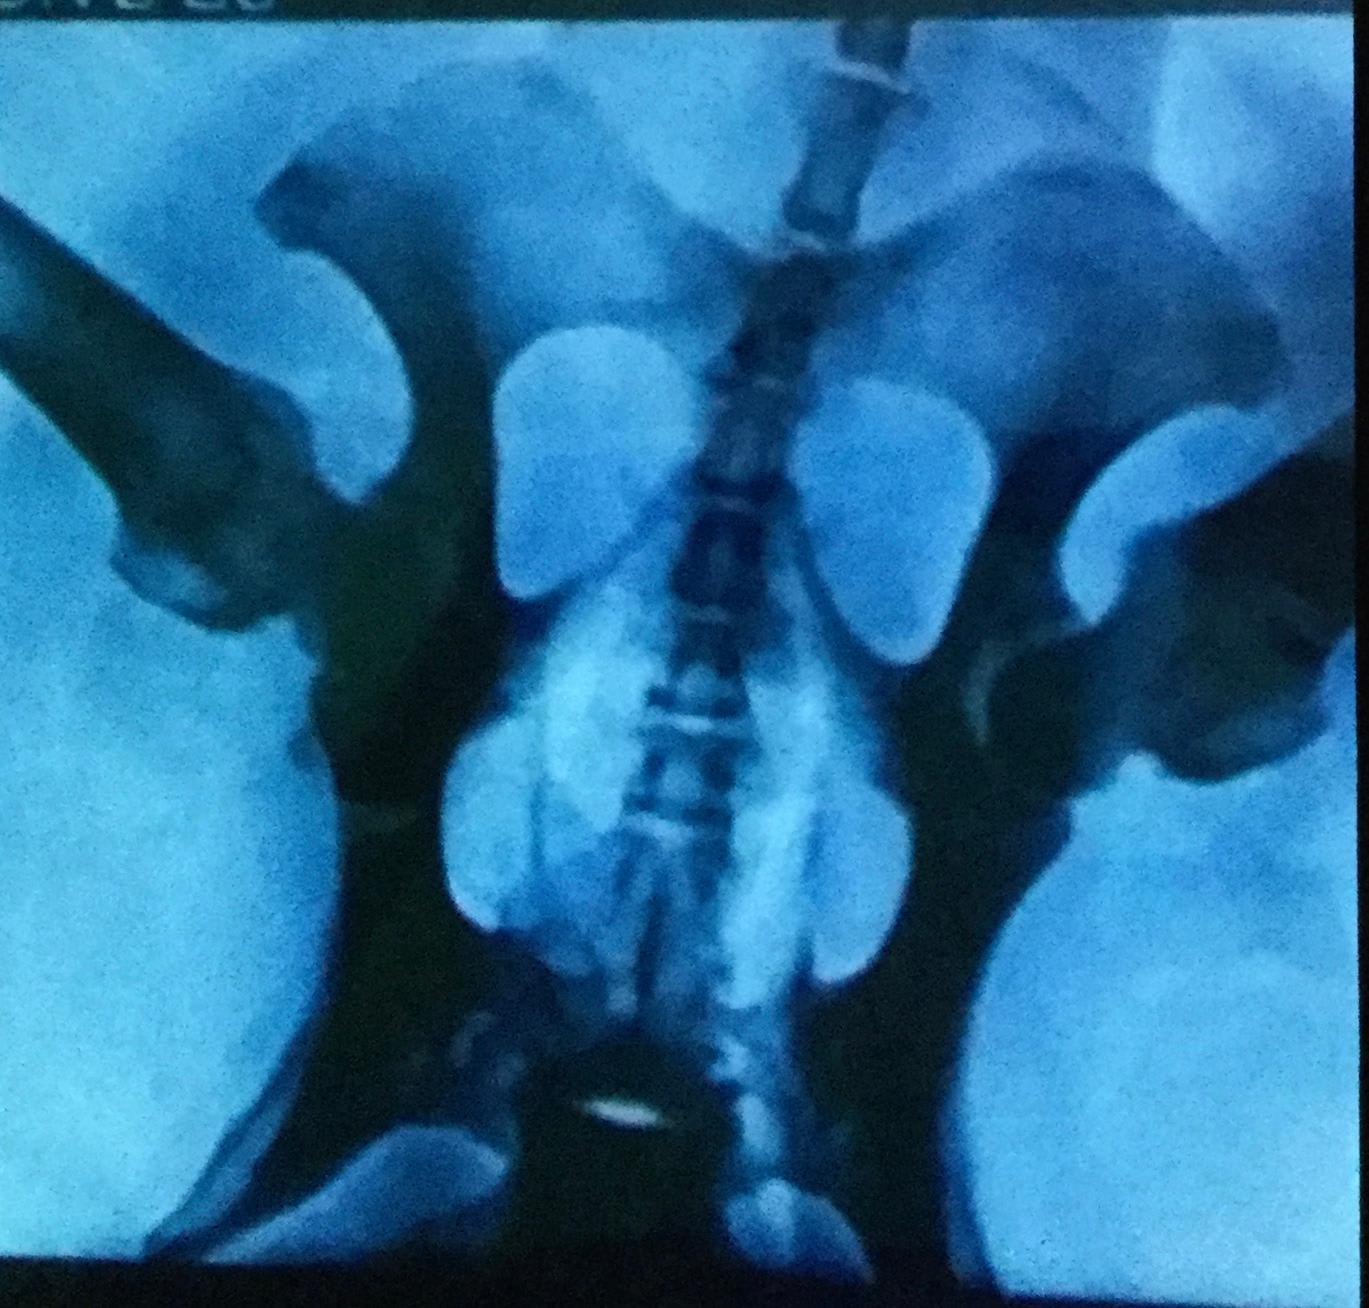

female Lab 10. Cannot put her hind left leg down. Since past 7 yrs it’s getting worse. Earlier she was active . The vet did physical examination and these xrays but have not come to a conclusion if it’s hip dysplasia, muscle myopathy or arthritis. Initially we put her on Dasuquin with MSM to which she responded . At present we are giving her Beaphar HD and Kalk tabs. Also Condrovet Force HA, Nurokind-Pet and Digene antacid. I want diagnosis and what treatment to be given . Please help. Desperate

Hello. The hips do look pretty good. I would ask your veterinarian to examine & determine if it is possible that Zoi has injured her knee. I would be especially interested in your vet conducting an exam looking for a cranial drawer sign that would indicate an anterior cruciate ligament tear, a common injury in larger breed dogs. Hope you find an answer to Zoi's pain & discomfort & thanks for using Petco Pet Education Center, formerly Petcoach.